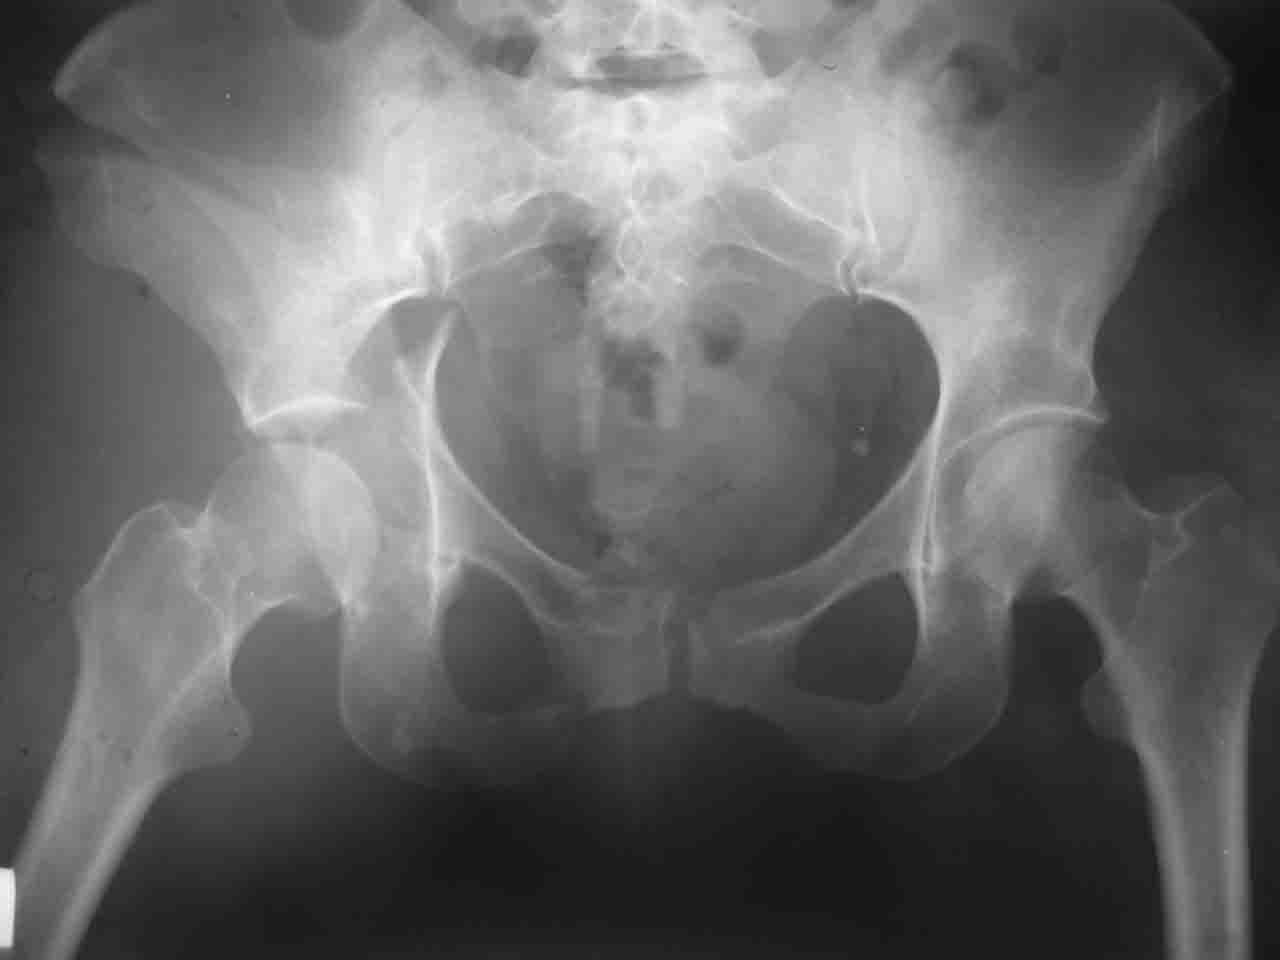

> А какой отдел вертлужной впадины более важен - передний или задний?

Однозначного ответа у меня нет : лучше быть богатым и здоровым , чем бедным и больным :-))

Логика подсказывает, что все-таки лучше иметь анатомически полноценную впадину, хотя ранее упоминалось состояние вторичной конгруэнтности и одно наблюдение у меня есть, когда у больного с полностью нарушенной анатомией впадины и подвывихом головки бедра кзади и кверху боли отсутствовали при относительно достаточном для стиля жизни больного объёме движений. Но это только одно наблюдение и кроме перелома впадины у этогобольного была и тяжелая ЧМТ в анамнезе. Основываясь на формулировке структуры ацетабулюм Э. Летурнеля - как перевернутой буквы Y, впадина для полноценной функции сустава должна иметь сферичность, соответствующую размеру головки бедра и если один из компонентов в дефиците, то функциональные последствия рано или поздно проявятся.